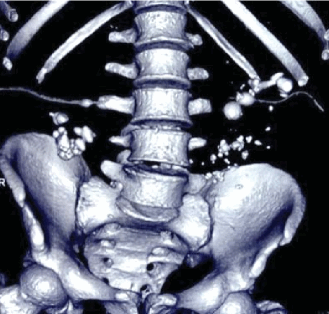

(Слева) Внутривенная пиелография в экскреторную фазу, прямая проекция: несколько пристеночных дефектов наполнения небольших размеров в левом мочеточнике, в проксимальном его отделе и в середине. Эти признаки характерны для кистозного уретерита.

(Справа) КТ-урография, реконструкция в плоскости наибольшей интенсивности, корональный срез: у пожилого мужчины с дизурией и предшествующими эпизодами инфекции вдоль правого мочеточника определяются несколько дефектов наполнения с ровным контуром На эндоскопии выявлено, что данные образования находятся в подслизистом слое, а в образцах биопсии отсутствовали признаки переходноклеточного рака.

Поэтапно выполнена перкутанная нефролитотомия с обеих сторон. Конкременты удалены полностью. На фоне билатерально установленных внутренних мочеточниковых стентов добиться регрессии кистозных элементов не удалось. Произведен поочередно полная эндоскопическая аблация кист мочеточников гольмиевым лазером (Ho:YAG) с диаметром волокна 365 μm, энергией 700 mJ и частотой 12 Hz. В послеоперационном периоде верхние мочевые пути дренировали внутренними мочеточниковыми стентами в течение 1-го месяца, после удаления которых восстановлен физиологический пассаж мочи по верхним мочевым путям. Несмотря на сохраняющуюся билатеральную гидронефротическую трансформацию (рис. 5), по данным динамической нефросцинтиграфии, отмечено умеренное нарушение накопительно-выделительной функции почек без признаков значимой обструкции. Уровень азотистых оснований сыворотки крови также оставался в пределах референтных значений.

Рисунок 5. АКТ экскреторной фазы после лечения

Figure 5. CT-scan of the excretory phase after the treatment